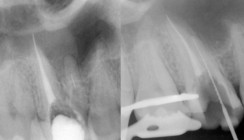

Tabelle 1 zeigt das Auftreten der Frakturen der Gruppe 1 (250 Fälle) in Anzahl pro Jahr nach der Behandlung. Insgesamt ereigneten sich bis zum siebten Jahr 21 vertikale Wurzelfrakturen. Die größte Anzahl findet sich im dritten und vierten Jahr. Es waren bis auf einen Fall alles Single-Visit-Behandlungen, die sich in 19 Erstzugänge (davon 14 Vitalextirpationen) und zwei Revisionen aufteilten. Es handelte sich um zwei Eckzähne, zehn Prämolaren und neun Molaren. Tabelle 2 zeigt das Auftreten der Frakturen der Gruppe 2 (250 Fälle) in Anzahl pro Jahr nach der Behandlung. Bisher trat in Gruppe 2 nur bei einem Fall eine Fraktur drei Jahre nach Therapie auf. Es handelte sich um einen Erstzugang eines devitalen Zahnes 25 mit Single-Visit-Behandlung. Die Nachbeobachtungszeit für diese Gruppe beträgt bisher sechs Jahre.

Es existieren einige In-vitro- und Finite-Element-Studien zum Thema, aber sehr wenig bzw. gar kein statistisches Material aus der Praxis. In Gruppe 1 ereigneten sich in den ersten sieben Jahren 21 Frakturen, in Gruppe 2 gab es nur eine. Der Unterschied in der Frakturinzidenz beider Gruppen ist erheblich. Das Hauptaufkommen der Frakturen findet sich in Gruppe 1 im dritten und vierten Jahr. Diese Häufung deckt sich mit den Berichten aus der Literatur. Bei der Forschung nach den Ursachen fällt innerhalb der Gruppe 1 auf, dass die im Jahr 2002 behandelten Zähne zu 14 Prozent eine Fraktur erlitten, die im Jahr 2003 behandelten aber nur noch zu 3,5 Prozent. 2002 wurde im März von Lupenbrille auf das Dentalmikroskop und im August die Spülungen von H2O2/NaOCl auf EDTA/NaOCl umgestellt. Darüber hinaus gab es am Behandlungsprotokoll in dieser Zeit keine Änderung. Von 16 Frakturfällen, deren Behandlung im Jahr 2002 erfolgte, fallen elf Fälle in die Zeit des H2O2/NaOCl-Spülprotokolls. In der Literatur wird der Einfluss verschiedener Spüllösungen auf die mechanischen Eigenschaften von Zähnen seit langer Zeit beschrieben. Ergebnisse, die den klinischen Einfluss der jeweiligen (miteinander kombinierten) Spüllösungen auf das spätere Auftreten von vertikalen Wurzelfrakturen erklären, sind mir nicht bekannt. Vergleicht man die beiden Gruppen, wurde die Umstellung von Instrumenten mit Radial-Land (ProFile) auf schneidende (ProTaper) und eine Umstellung von lateraler Kondensation auf vertikale mit erwärmter Guttapercha vorgenommen. In der Literatur finden sich klare Hinweise, dass das Dentin durch ProFile-Instrumente im Besonderen belastet wird. In der Bewertung der Relevanz der Fülltechniken im Hinblick auf Frakturen findet sich keine eindeutige Tendenz. Allerdings wird aktuell auf Kongressen über erschreckend hohe Frakturquoten nach endodontischen Therapien berichtet, bei denen laterale Kondensationen erfolgten. Neuere Untersuchungen diskutieren, dass okklusale Belastungen Frakturen begünstigen können. Bei Durchsicht aller endodontisch behandelten Zähne aus dem Jahr 2002, welche noch keine Krone hatten und Zahnersatz brauchten, fällt auf, dass die Zähne mit späterer Fraktur im Durchschnitt nach 15,6 Monaten, die Zähne ohne Fraktur nach 7,1 Monaten mit einer Krone versorgt wurden. Obwohl die einzelnen Variablen anhand dieser Daten nur schwer zu beurteilen sind, steht für mich fest – und das war damals die Hoffnung: Die Addition von Umstellung von ProFile auf ProTaper und von lateraler zu vertikaler Kondensation brachte eine signifikante Reduktion der Wurzelfrakturen.